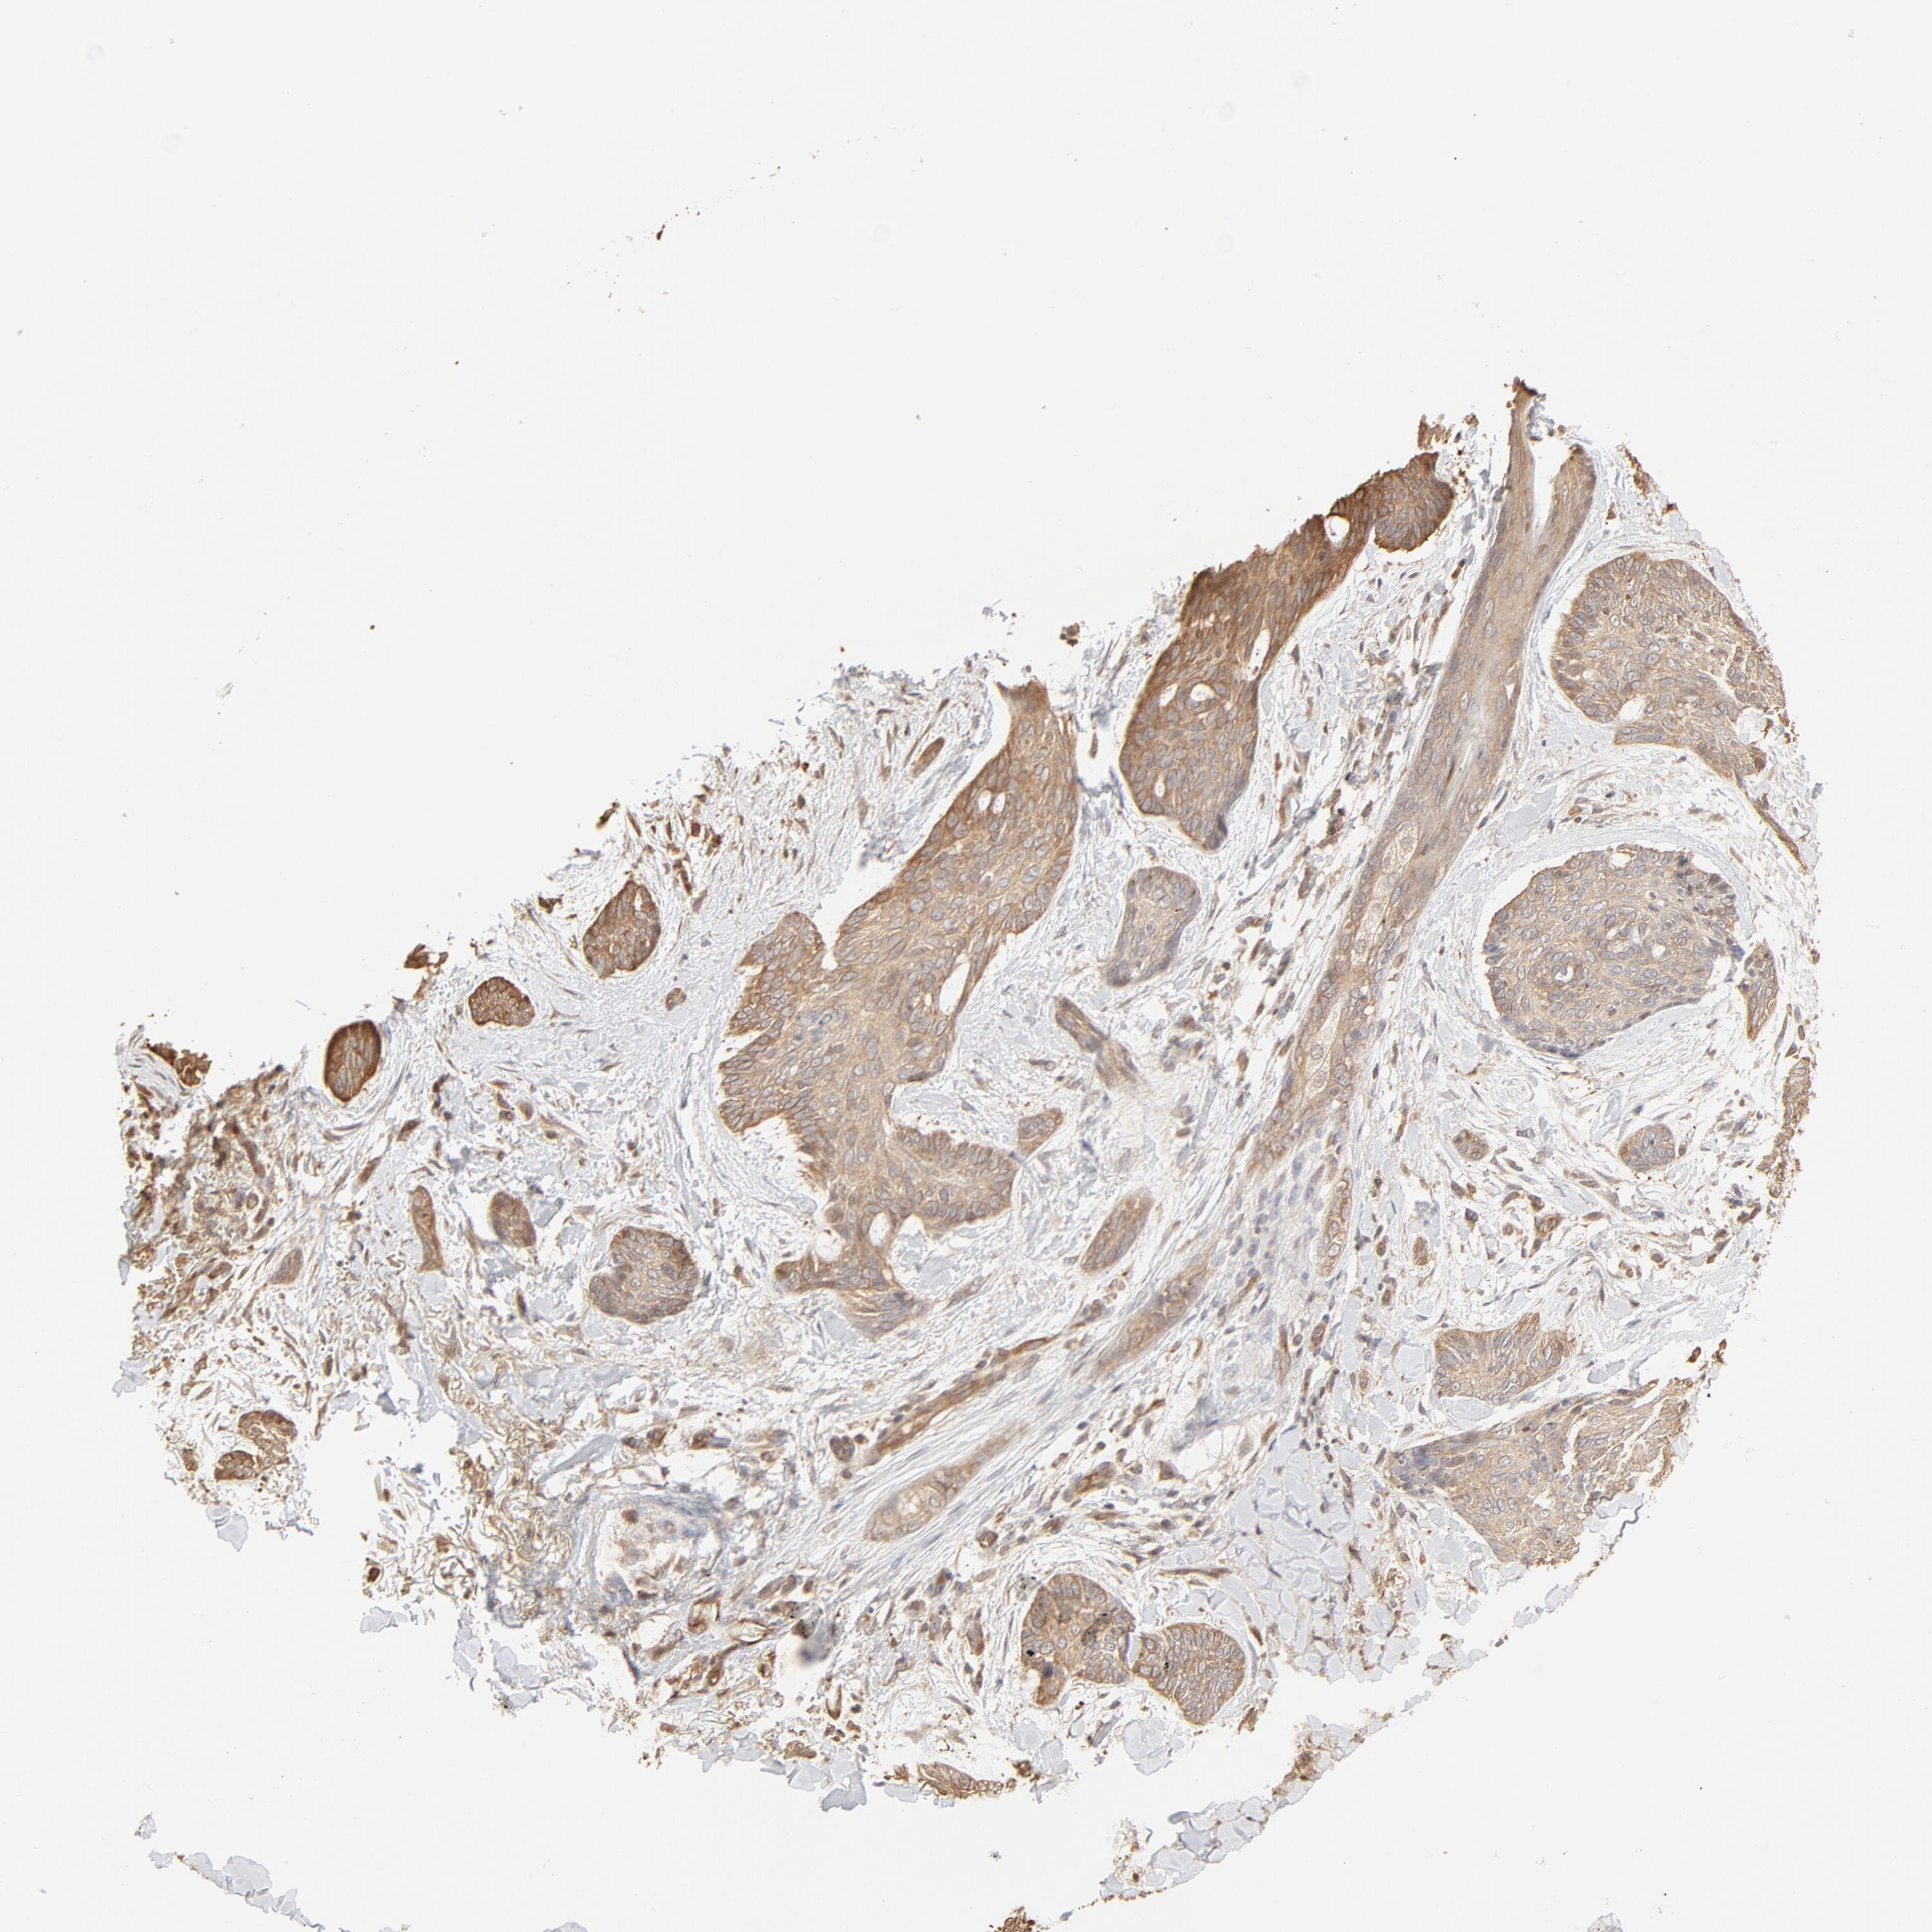

SKIN CANCER - Protein expressioni

A mouse-over function shows sample information and annotation data. Click on an image to view it in a full screen mode. Samples can be filtered based on level of antibody staining by selecting one or several of the following categories: high, medium, low and not detected. The assay and annotation is described here.

Antibody stainingi

Antibody staining in the annotated cell types in the current human tissue is reported as not detected, low, medium, or high, based on conventional immunohistochemistry profiling in selected tissues. This score is based on the combination of the staining intensity and fraction of stained cells.

Each image is clickable and will lead to virtual microscopy that enables deeper exploration of all samples and also displays staining intensity scores, fraction scores and subcellular localization as well as patient and tissue information for each sample.

Antibody CAB003848

Squamous cell carcinoma, NOS